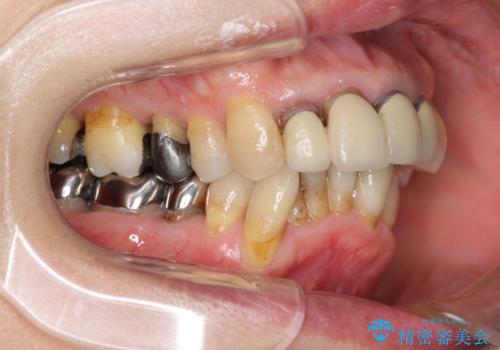

矯正を含む全顎治療

- 前歯の見た目・歯並び・銀歯の見た目の改善を求めて来院されました。

まずガタ付きの強い歯並びをマウスピース矯正インビザラインで整えたのち、セラミック治療による審美性の改善を計画します。